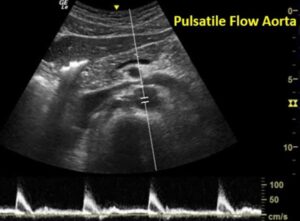

הדגמה נכונה ואופטימלית של האורטה הבטנית בשאלה של AAA היא חלק מ-LIFE SAVING POCUS.לפניכם סיכום